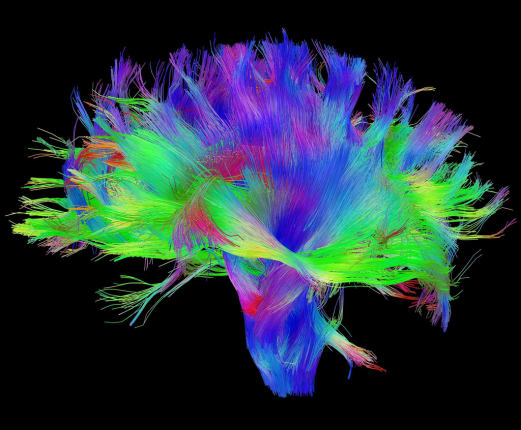

Diffusion Imaging

Tract Profile

AFQ-Browser

Yeatman, J. D., Richie-Halford, A., Smith, J. K., Keshavan, A., & Rokem, A. (2018). A browser-based tool for visualization and analysis of diffusion MRI data. Nature communications, 9(1), 940.

- We need to easily explore data

- We need to easily share data

- tabular data

Web Technology

Domain Science

pip install AFQ-Browser

afqbrowser-assemble /path/to/afq.mat

afqbrowser-publish /path/to/target/ reponame

Easy to Share